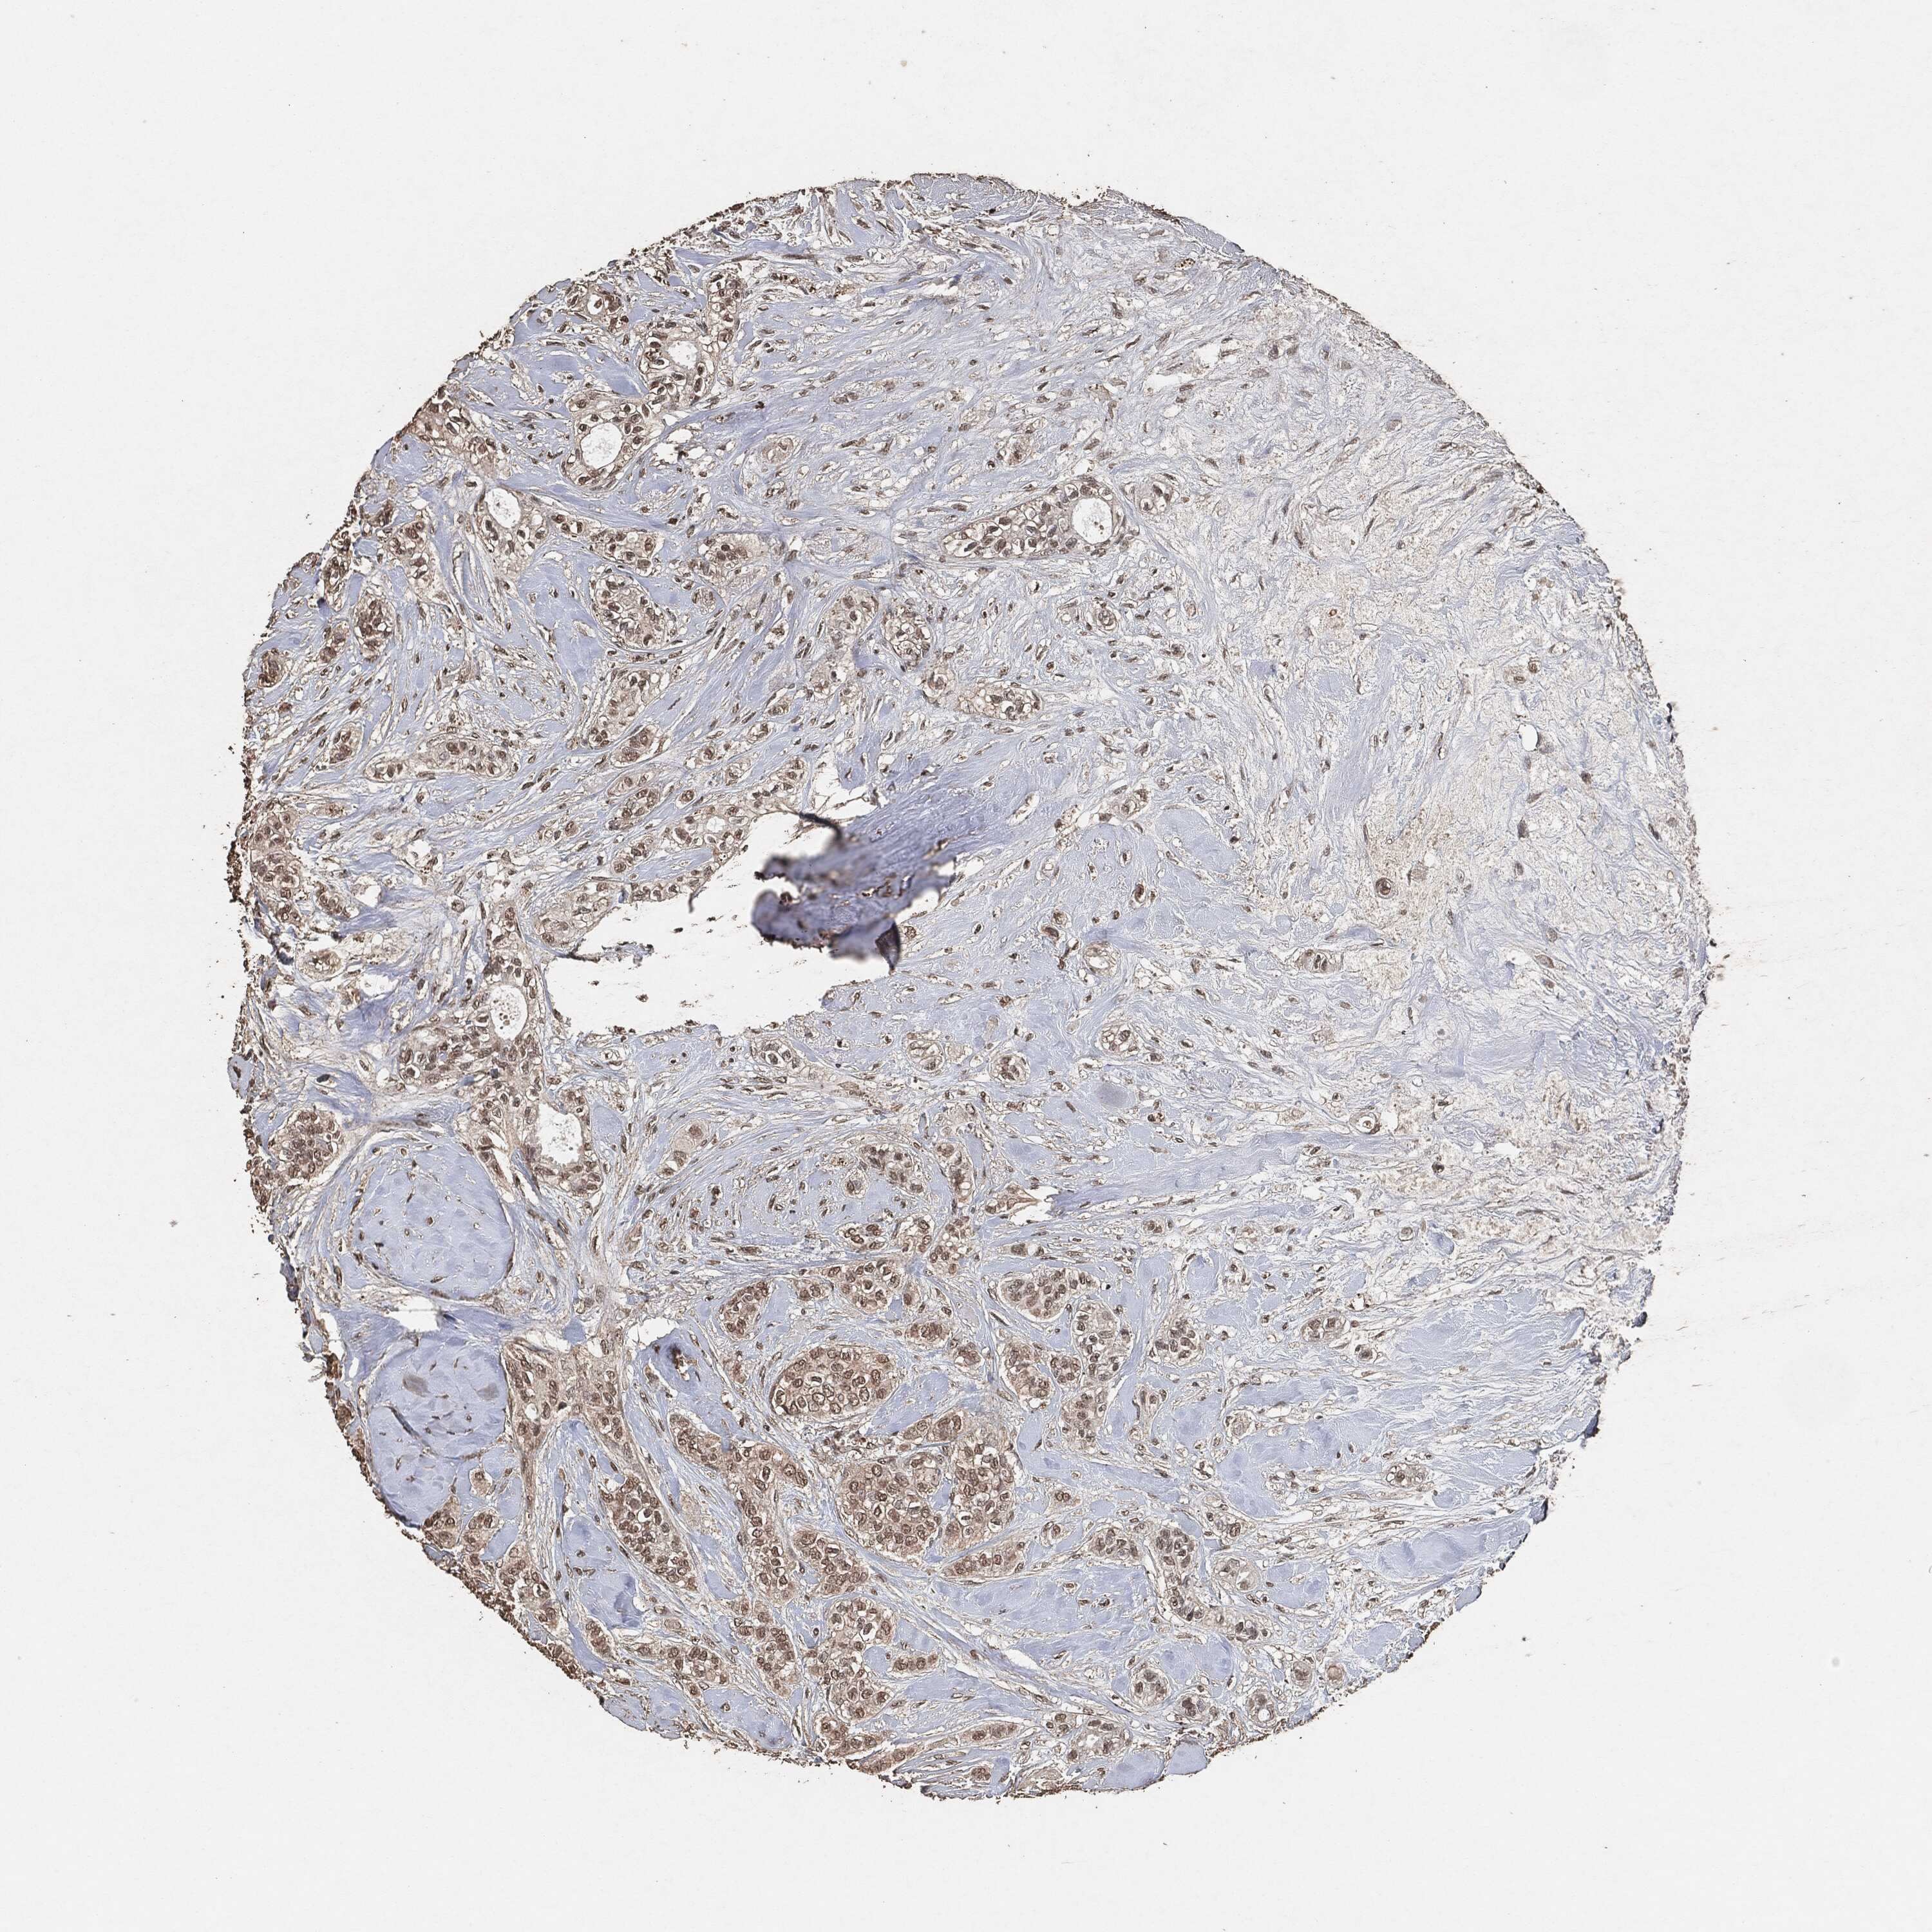

CANCER BREAST CANCER Show tissue menu

BRCA TCGA BRCA VALIDATION PROTEIN EXPRESSION

ANTIBODIES

AND

VALIDATION